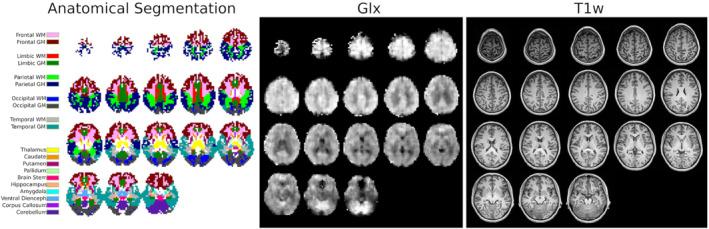

There is a growing interest in the neuroscience community to map the distribution of brain metabolites in vivo. Magnetic resonance spectroscopic imaging (MRSI) is often limited by either a poor spatial resolution and/or a long acquisition time, which severely restricts its applications for clinical and research purposes. Building on a recently developed technique of acquisition-reconstruction for 2D MRSI, we combined a fast Cartesian H-FID-MRSI acquisition sequence, compressed-sensing acceleration, and low-rank total-generalized-variation constrained reconstruction to produce 3D high-resolution whole-brain MRSI with a significant acquisition time reduction. We first evaluated the acceleration performance using retrospective undersampling of a fully sampled dataset. Second, a 20 min accelerated MRSI acquisition was performed on three healthy volunteers, resulting in metabolite maps with 5 mm isotropic resolution. The metabolite maps exhibited the detailed neurochemical composition of all brain regions and revealed parts of the underlying brain anatomy. The latter assessment used previous reported knowledge and a atlas-based analysis to show consistency of the concentration contrasts and ratio across all brain regions. These results acquired on a clinical 3 T MRI scanner successfully combined 3D H-FID-MRSI with a constrained reconstruction to produce detailed mapping of metabolite concentrations at high resolution over the whole brain, with an acquisition time suitable for clinical or research settings.

神经科学界越来越有兴趣在体内绘制脑代谢物的分布图。磁共振波谱成像(MRSI)通常受到空间分辨率差和/或采集时间长的限制,这严重限制了其在临床和研究中的应用。基于最近开发的二维 MRSI 采集-重建技术,我们结合了快速笛卡尔 H-FID-MRSI 采集序列、压缩感知加速和低秩全广义变分约束重建,以产生具有显著采集时间减少的 3D 高分辨率全脑 MRSI。我们首先使用完全采样数据集的回顾性欠采样来评估加速性能。其次,在三个健康志愿者上进行了 20 分钟的加速 MRSI 采集,得到了具有 5mm 各向同性分辨率的代谢物图。代谢物图显示了所有脑区的详细神经化学组成,并揭示了部分脑内解剖结构。后者评估使用了先前报道的知识和基于图谱的分析,以显示所有脑区的浓度对比和比值的一致性。这些在临床 3T MRI 扫描仪上获得的结果成功地将 3D H-FID-MRSI 与约束重建相结合,在整个大脑中以高分辨率产生代谢物浓度的详细映射,采集时间适合临床或研究环境。